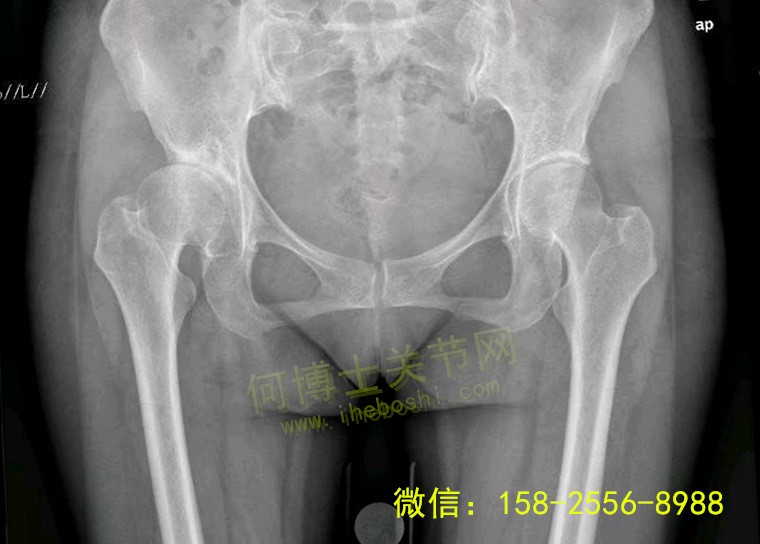

术前片子:诊断为先天性髋关节发育不良

20180517162029042904.jpg